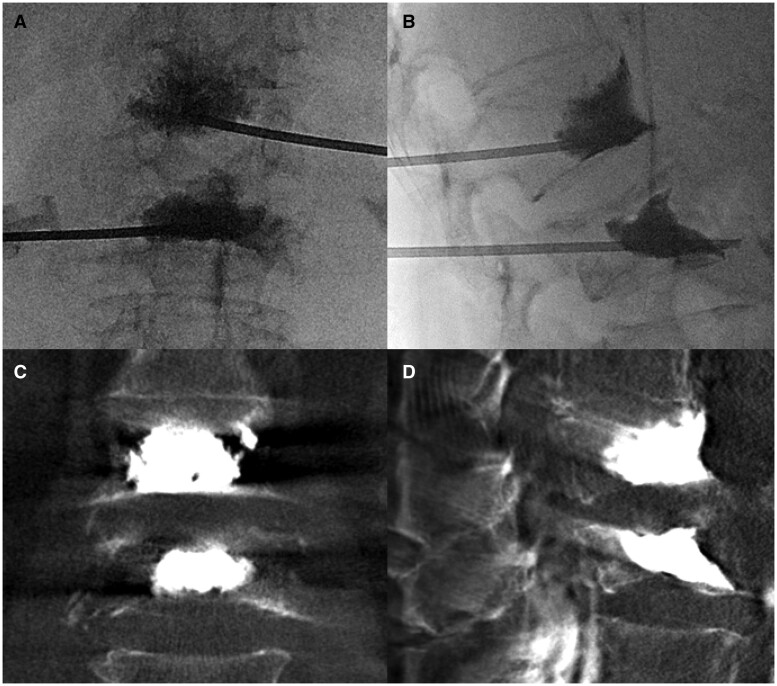

Abstract Image